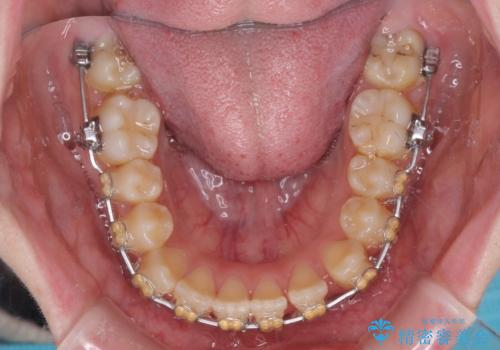

- 矯正装置

- 審美装置

舌の突出癖があり、それが原因で上下前歯に隙間ができていたため、改善のためのトレーニングを行うように指示をしました。

舌の突出癖の影響か、なかなかスペースが閉じきらず、治療期間は予定よりも長期間となりました。

舌突出癖改善のトレーニングの重要性を認識することとなりました。